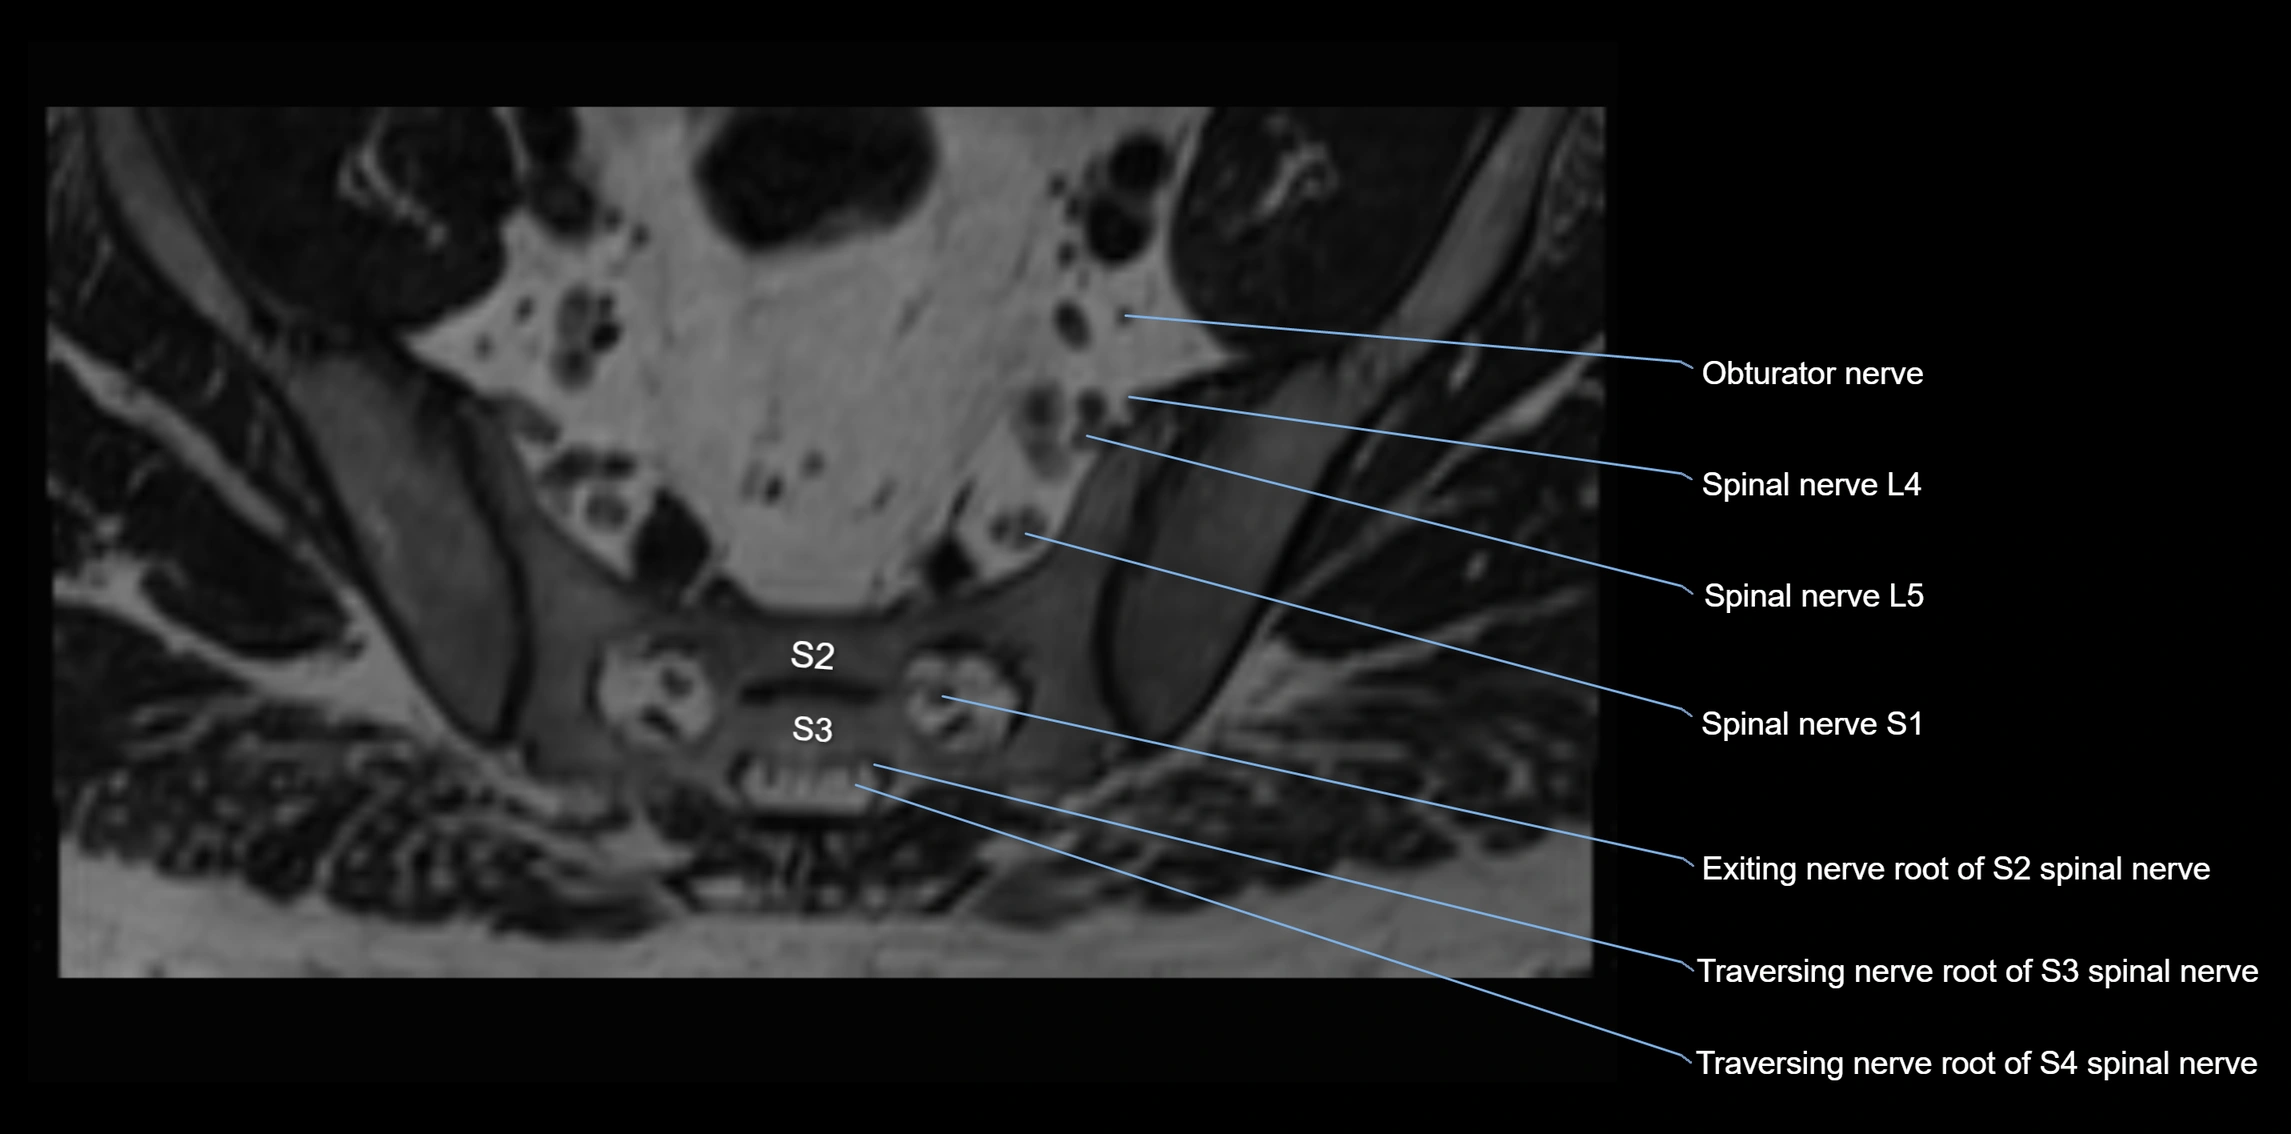

MRI image

image